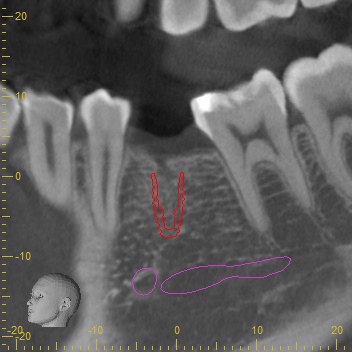

CTスキャンによるシュミレーション

永久歯がもともとないところは骨のボリュームが足りないことがほとんどです。

今回もCTスキャンで調べるとインプラントの外側に骨が足りないことが分かりました。足りない量がそれほど多くなかったためにインプラント埋め込みと同時に骨補填材を移植して骨造成をすることになりました。